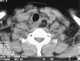

Fibrovascular polyp